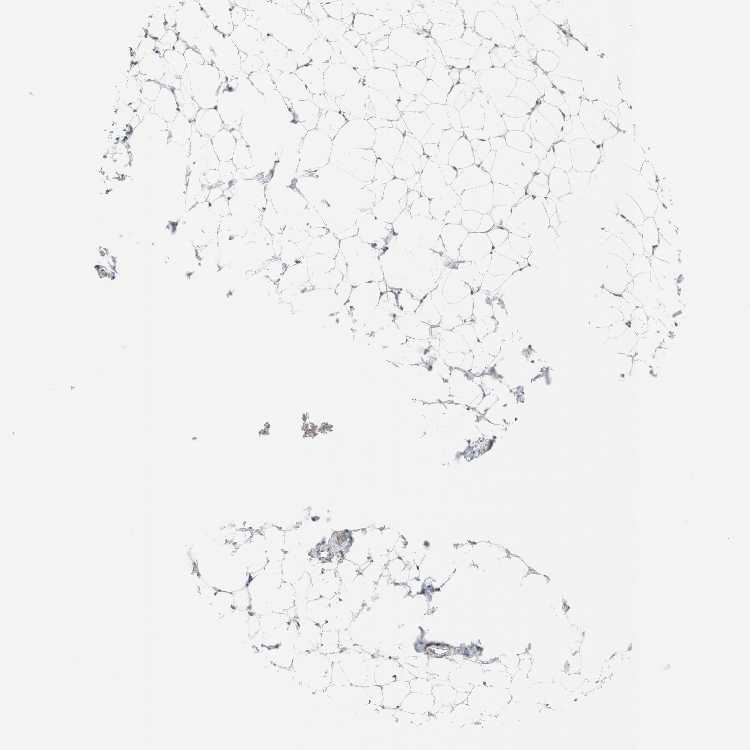

TISSUE PRIMARY DATA SOFT TISSUE Show tissue menu

SOFT TISSUE - Expression summary

SOFT TISSUE 1 - Antibody stainingi

Antibody staining in the annotated cell types in the current human tissue is reported as not detected, low, medium, or high, based on conventional immunohistochemistry profiling in selected tissues. This score is based on the combination of the staining intensity and fraction of stained cells.

Each image is clickable and will lead to virtual microscopy that enables deeper exploration of all samples and also displays staining intensity scores, fraction scores and subcellular localization as well as patient and tissue information for each sample.

Antibody HPA002238Antibody HPA005958Antibody CAB006271

Chondrocytes -Not detectedNot detected

Fibroblasts LowNot detectedLow

SOFT TISSUE 2 - Antibody stainingi

Fibroblasts LowNot detectedMedium

Peripheral nerve LowNot detectedLow